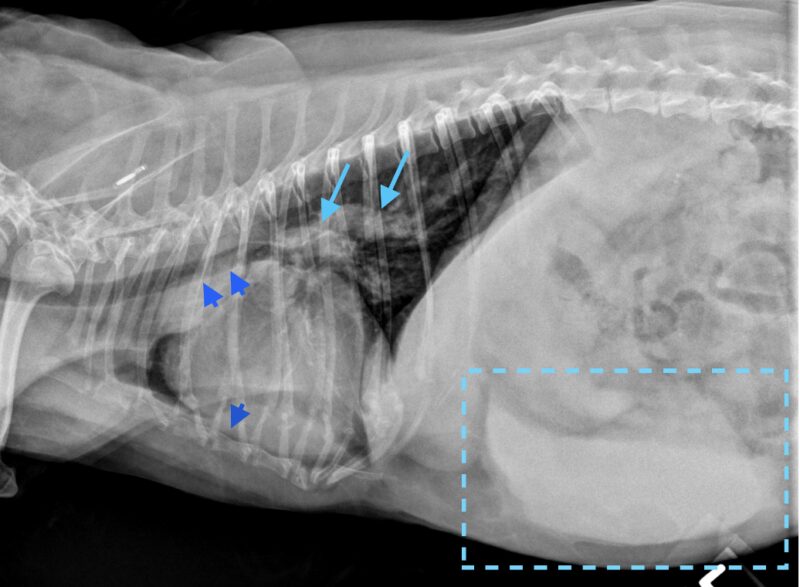

Dr. Anna Adrian, MS, DACVR, antwortet: Vielen Dank für die Zusendung dieses interessanten Falles. Es liegen eine links- und rechtslaterale sowie eine ventrodorsale Thoraxaufnahme vor. In allen drei Projektionen zeigt sich eine ausgeprägte rechtsseitige Kardiomegalie, die mit einer dorsalen Verlagerung der Trachea sowie einem vermehrten Kontakt des Herzens zum Sternum einhergeht (Bild 1, dunkelblaue Pfeilköpfe). In der ventrodorsalen Projektion imponiert die Rechtsherzvergrößerung als typische „reverse D-Form“ (Bild 2, dunkelblaue Pfeile). Zusätzlich fällt in dieser Ansicht auf Höhe der 2-Uhr-Position eine Vorwölbung auf, die einer Dilatation des Truncus pulmonalis entspricht (Bild 2, dunkelblauer Kreis).

Die kaudalen lobären Pulmonalarterien sind hochgradig erweitert, überschreiten deutlich die Breite der 9. Rippe und zeigen einen geschlängelten Verlauf (Bild 1 und 2, hellblaue Pfeile). Zur Erinnerung Venen liegen in der VD-Aufnahme zentral und in der lateralen Aufnahme ventral, wohingegen Arterien lateral und dorsal gelegen sind. Die Vena cava caudalis erscheint geringgradig dilatiert. Das Lungenparenchym weist insgesamt ein leicht- bis mittelgradig ausgeprägtes bronchointerstitielles Muster auf. Im kranialen Abdomen ist eine kraniale abdominale Organomegalie erkennbar, sowie geringgradige Heterogenität des abdominalen Fettgewebes (Bild 1, hellblau gestricheltes Rechteck). Dieser Befund ist vereinbar mit einer Splenomegalie +/- Hepatomegalie und geringgradiger Aszites. Die übrigen abdominalen Strukturen erscheinen unauffällig.

Zusammenfassend liegen eine ausgeprägte rechtsseitige Kardiomegalie sowie eine deutliche Erweiterung der Pulmonalarterien vor. Die Befundkonstellation spricht für eine pulmonale Hypertension in Kombination mit einer Kardiomyopathie, möglicherweise sekundär infolge einer Herzwurmerkrankung oder eines idiopathischen Cor pulmonale. Zur weiterführenden Abklärung wird eine echokardiographische Untersuchung empfohlen. Das bronchointerstitielle Lungenmuster kann altersphysiologisch bedingt sein, differentialdiagnostisch sind jedoch auch eosinophile Infiltrate im Rahmen einer parasitär bedingten Hypersensitivitätsreaktion in Betracht zu ziehen. Die Dilatation der Vena cava caudalis kann einerseits ein Normvariant darstellen, andererseits im Kontext der Rechtsherzvergrößerung auf eine Rechtsherzinsuffizienz oder ein Vena-cava-Syndrom bei hoher parasitärer Last hinweisen.

Die vermutete Splenomegalie +/- Hepatomegalie kann ebenfalls als Folge einer venösen Kongestion bei Rechtsherzversagen oder Vena-cava-Syndrom interpretiert werden. Weitere Differenzialdiagnosen umfassen entzündliche Veränderungen (Hepatitis, Splenitis), sowie neoplastische Infiltrationen. Die geringgradige abdominale Effusion Zur weiteren Abklärung wird eine abdominale Ultraschalluntersuchung empfohlen.